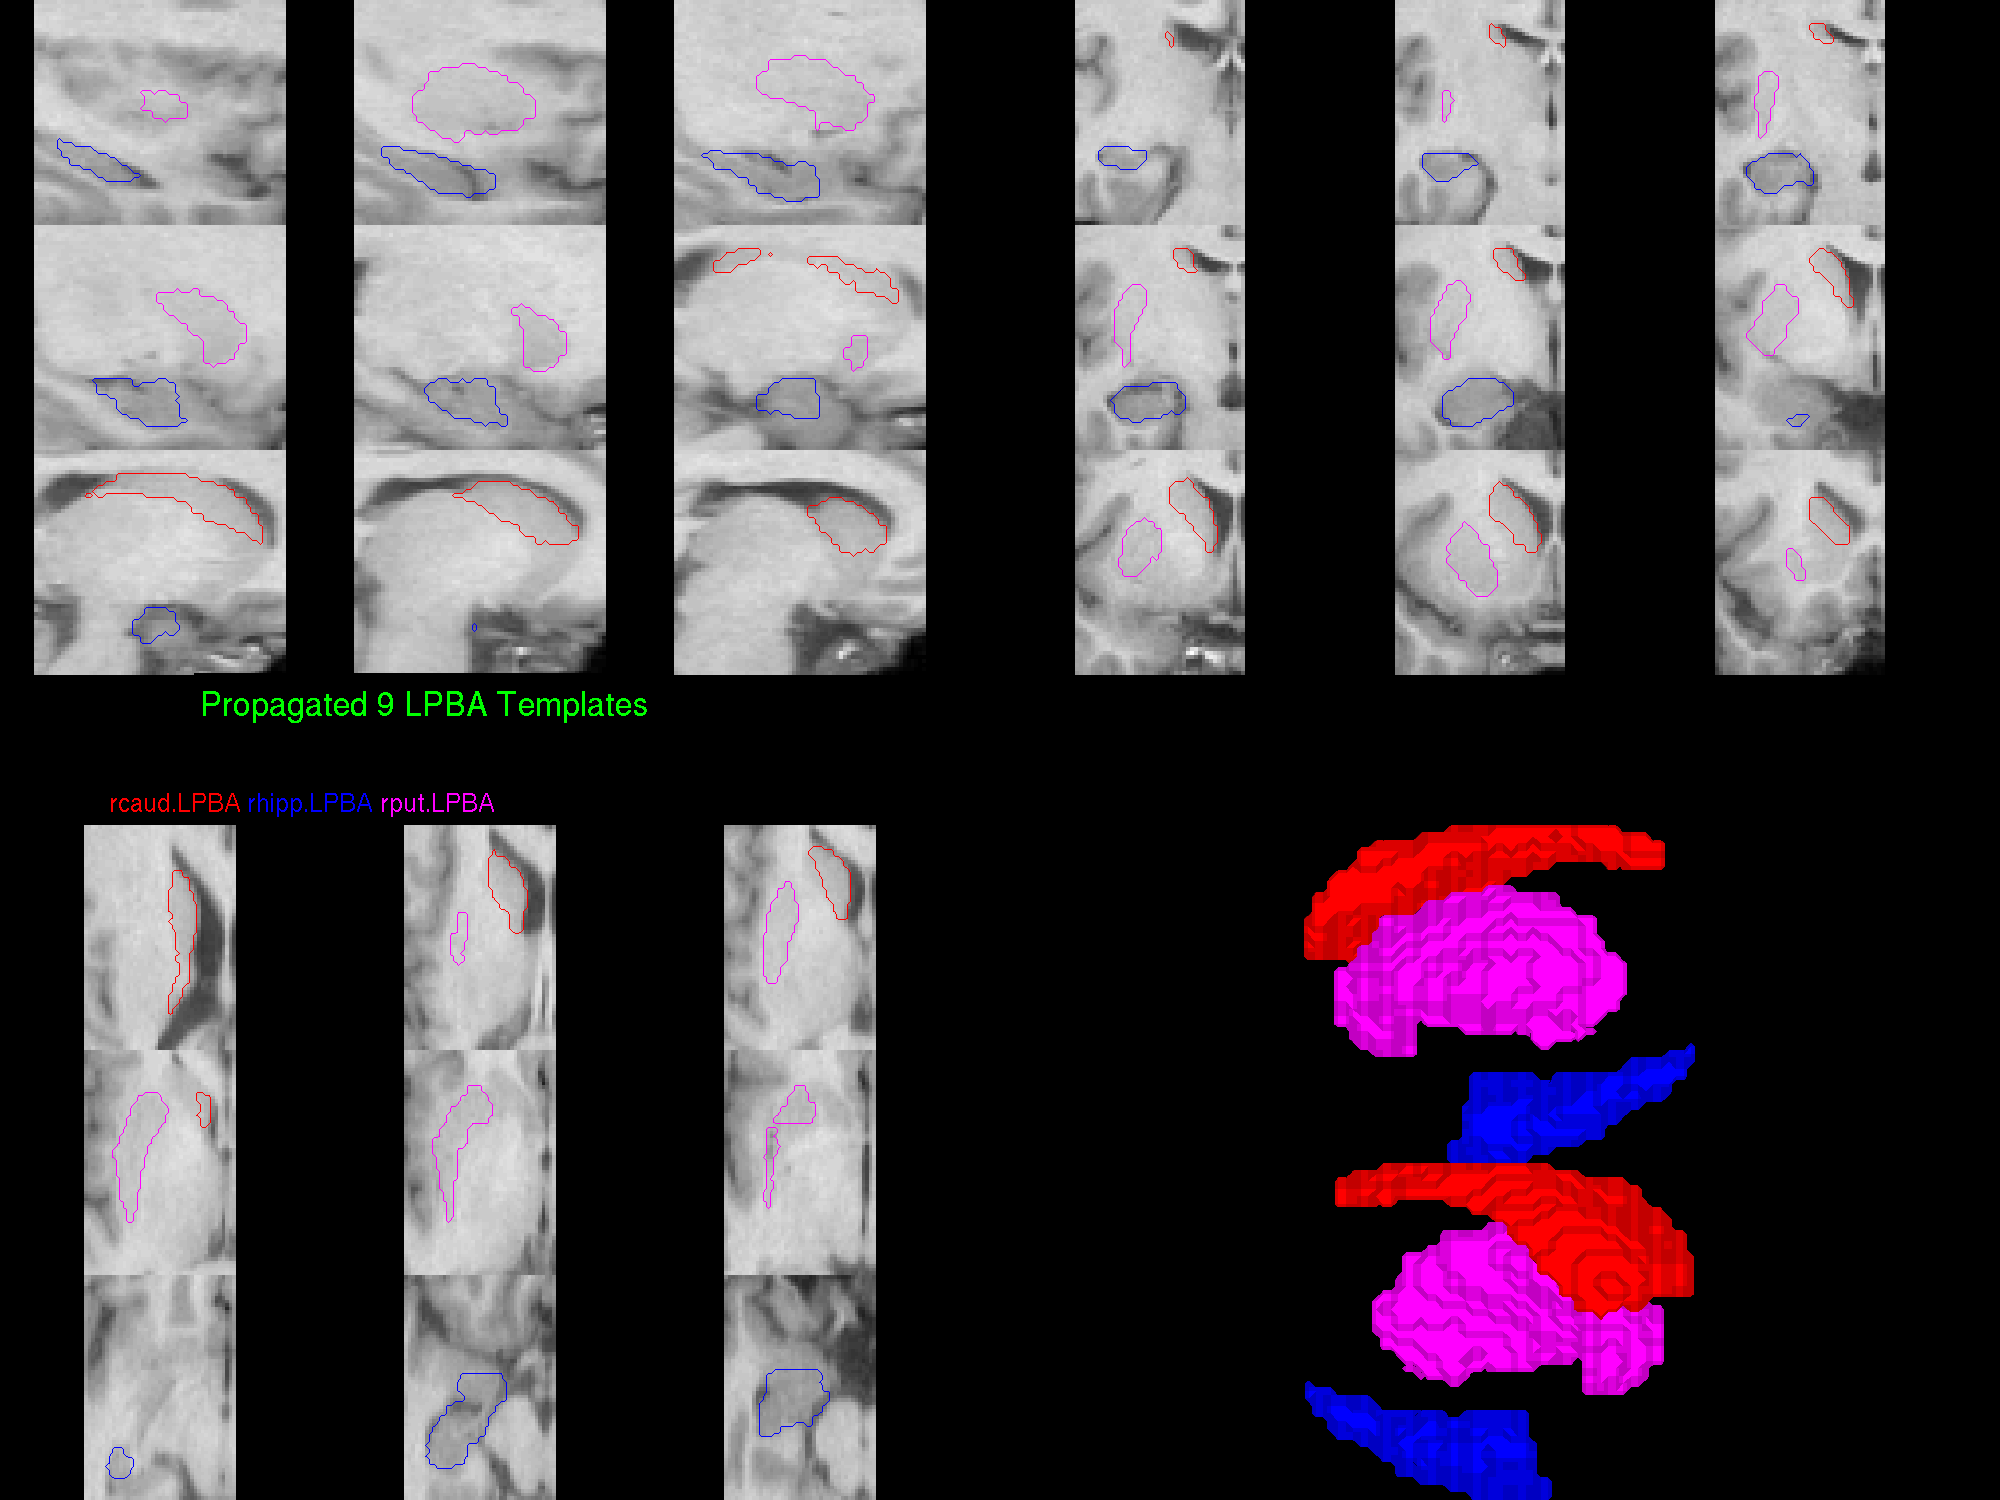

LPBA Segmentations using 9 LPBA templates

Caudate, Putamen, Hippocampus in Alzheimer's patients (Multi-atlas propagation)

Left Caudate, Putamen, Hippocampus

Right Caudate, Putamen, Hippocampus